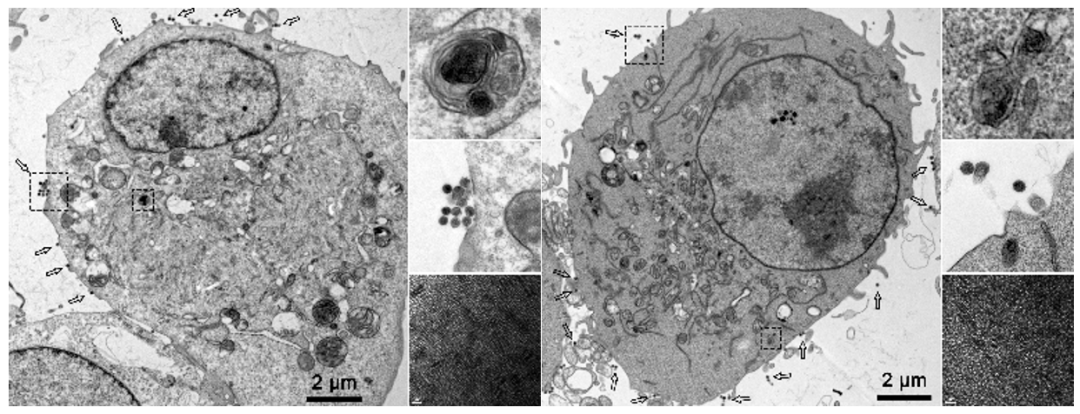

此外,高会乐教授团队通过建立基于器官芯片的体外血脑屏障模型,证实纳米递药系统可通过跨血脑屏障主动转运出脑(图2)(其中图2(A)是血脑屏障器官芯片示意图,图2(B)是两种金纳米簇跨越血脑屏障模型的过程)。通过小鼠体内模型还验证了转运过程依赖外泌体的分泌过程(图3)。

图2  纳米递药系统可通过跨血脑屏障主动转运出脑

图3  外泌体负责携带内皮细胞中的金纳米簇出胞

小胶质细胞作为脑内的巨噬细胞,也对脑靶向纳米递药系统的排泄清除具有促进作用(图4)。但作为脑内常驻细胞,小胶质细胞不具备携带纳米递药系统出脑的能力,因此高会乐教授团队推测其可将吞噬收集的纳米递药系统呈递给其他排泄途径,而达到促进排泄的效果,这一猜想也在随后的实验中得到了验证(图5、图6)。